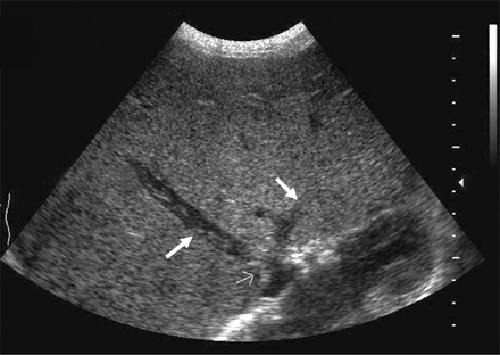

What is Portal venous hypertension?

This is an increase in portal venous pressure (above 10mmHg) or hepatic venous gradient (above 5mmHg).

What is the sonographic appearance of Portal venous hypertension?

Portal vein measures greater than 13mm

Collateral

circulation

Flow reversal

Ascites

Hepatosplenomegaly

What are the presenting symptoms of Portal venous hypertension?

Gastrointestinal bleeding

blood in the stools

vomiting of blood

Encephalopathy

What are the lab values that would suggest Portal venous hypertension?

↑Liver Enzymes

↓Platelet Count